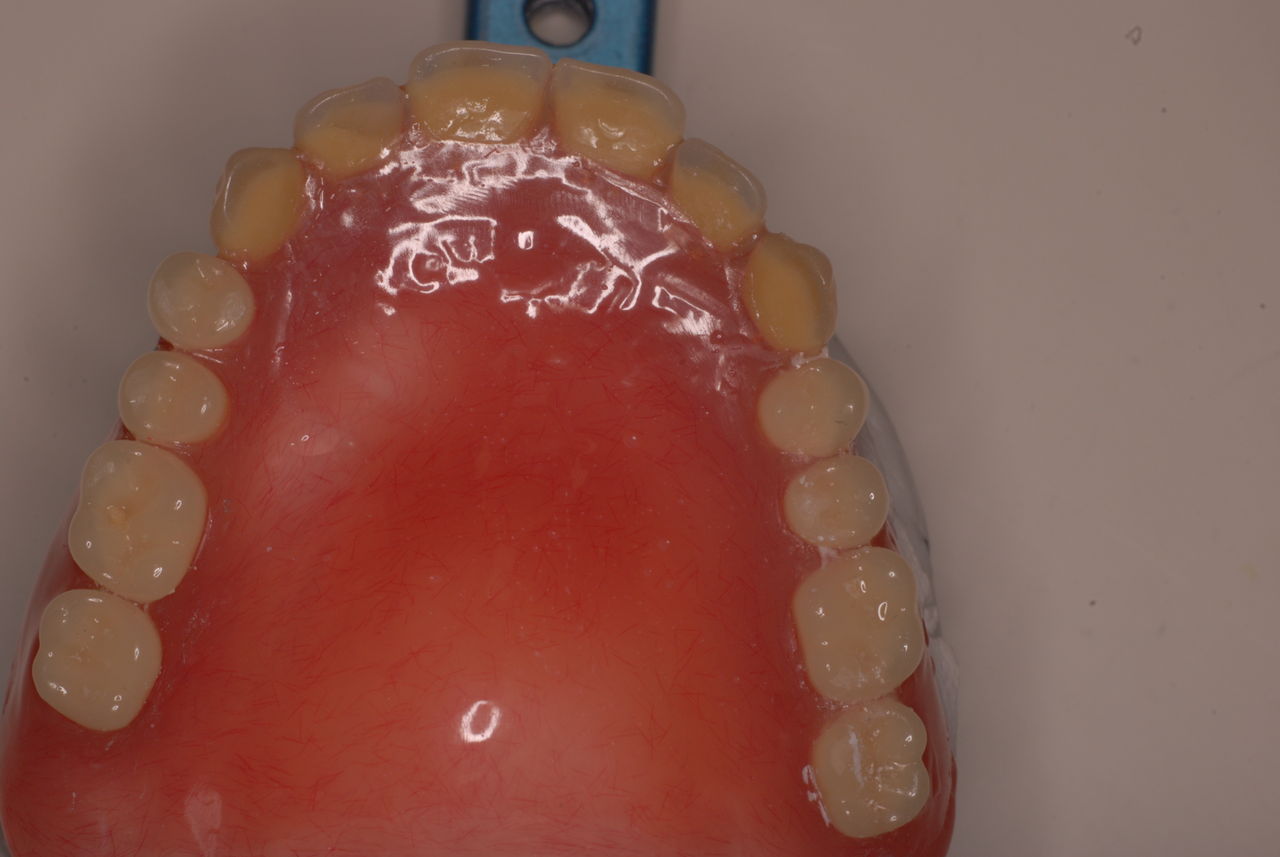

上の総義歯はまっったくはずれませんでした。下顎の入れ歯では若干痛みが出そうなので噛み合わせの調整をしています。口腔内では時間がかかりすぎるので器械に付けて調整しています。